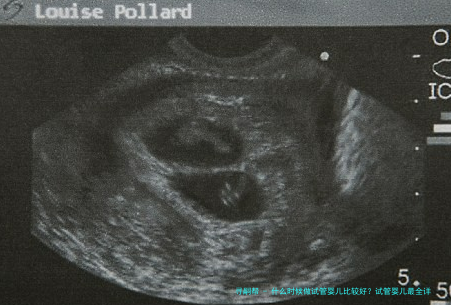

接下来要做的便是促排卵以及监测卵泡,一般来说在黄体的中期也就是月事的第二十一天的时间,就可以开始使用药物,让整个体内的促性腺激素身在一种较低的水准,用药八日左右,基本上也全部是例假来潮,如此整个例假的第3天到第7天开始做好肌肉注射,并且能够做好促卵泡的发育,三天其后的B超检测卵泡生长状况,能够有效调治所有的用药剂量。

在试管婴儿手术实施过程中,可以通过超声疏导下来做促排卵和提炼精子,在体外进行受精,培育72小时随后发育好的受精卵就可以放到胚胎当中,紧接着就能够做子宫腔的移植。如果是第3代试管婴儿的话,还需要做胚胎保存。

女方把握性超排卵,借助B超和血检监测卵泡动向生长;

试管受孕,即将精卵放在体外培育皿中自由结合或者根据须要人工将精子注射进卵子,历经受精、卵裂,体外发育3天(第三日胚胎)要不5-6天(囊胚);